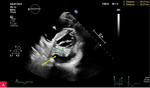

Rycina 1A, B. Zwapnienie w pierścieniu mitralnym (MAC) u podstawy tylnego płatka mitralnego w projekcji przymostkowej w osi długiej LAX (A) i w osi krótkiej SAX (B)

Zwapnienie pierścienia zastawki mitralnej (MAC – mitral annular calcification) stanowi następstwo przewlekłych zmian degeneracyjnych i jest dość często spotykane u osób w starszym wieku (ryc. 1). Serowate zwapnienie pierścienia mitralnego (CCMA – caseous calcification of the mitral annulus) to rzadki, często niedostatecznie rozpoznawany wariant MAC. CCMA stanowi ok. 0,6% wszystkich przypadków MAC, występuje rzadziej niż w 0,1% populacji ogólnej. Częściej dotyka starszych kobiet, szczególnie z nadciśnieniem tętniczym, przewlekłą chorobą nerek lub zaburzeniami gospodarki wapniowo-fosforanowej1,2. Zmiana zazwyczaj obejmuje tylny pierścień zastawki mitralnej i składa się z uwapnionej otoczki oraz wnętrza wypełnionego mieszaniną wapnia, kwasów tłuszczowych i cholesterolu, przypominającą konsystencją pastę do zębów3,4. CCMA może osiągać duże rozmiary, szerząc się w kierunku tylnego płatka mitralnego oraz mięśnia lewej komory w zakresie ściany dolno-bocznej i dolnej.